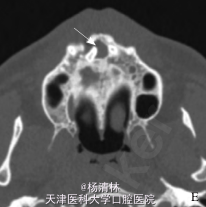

检查:12、11牙间的前庭沟区肿胀、压痛、触及囊性感;肿胀区相关牙未见龋坏、变色及异常松动,牙髓电活力检测试验反应正常。辅查:穿刺细胞学检查:穿刺得脓性囊液,涂片镜检见胆固醇结晶。 CT 示:左、右上中切牙与侧切牙之间根尖平面以上,骨组织内对称性分布的 2 枚多生牙;右侧见低密度囊性影,且多生牙包含其中。

诊断:上颌骨前部骨埋伏阻生多生牙并右侧含牙囊肿。处理:控制伴发的继发性感染后于局麻下行囊肿刮治及骨埋伏阻生牙拔除术,术后 7 d 治愈出院。

手术标本行常规石蜡包埋切片,病理表现为薄层复层鳞状上皮增生,钉突明显,纤维壁内见大量炎细胞浸润,病理诊断为含牙囊肿伴感染。 锥形束 CT 可以对颌骨病变,特别是多生牙的三维定位提供更全面、更准确的诊断依据,清晰地显示阻生牙的唇腭向、颊腭向、垂直向位置关系,并可以测量阻生牙与上颌窦、下颌神经管等重要解剖结构之间的距离,以确保手术安全,同时锥形束 CT 较普通 CT 具有辐射低、空间分辨率高的优点(病例来源于网络)